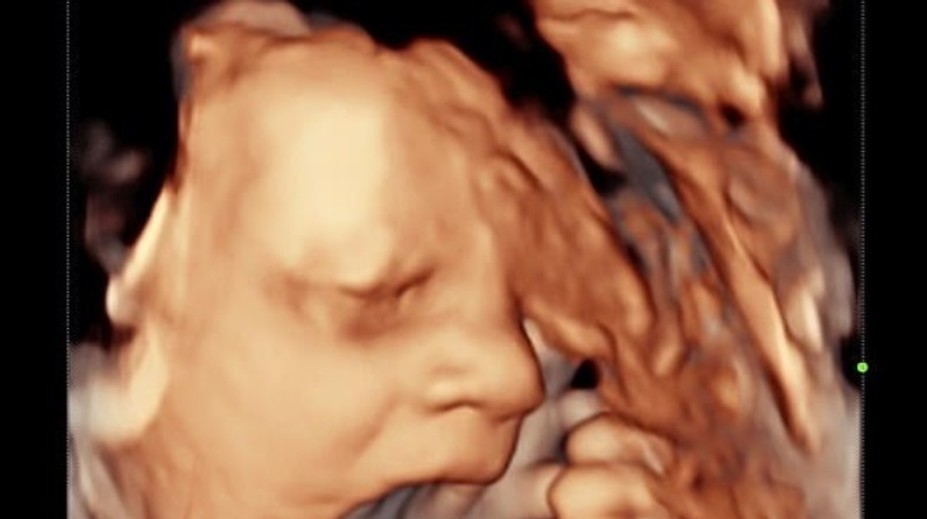

Pár počas predpôrodného ultrazvuku zostal v nemom úžase. Bábätko ukázalo šokujúce gesto Róbert Ďurkáč 27. 10. 2020